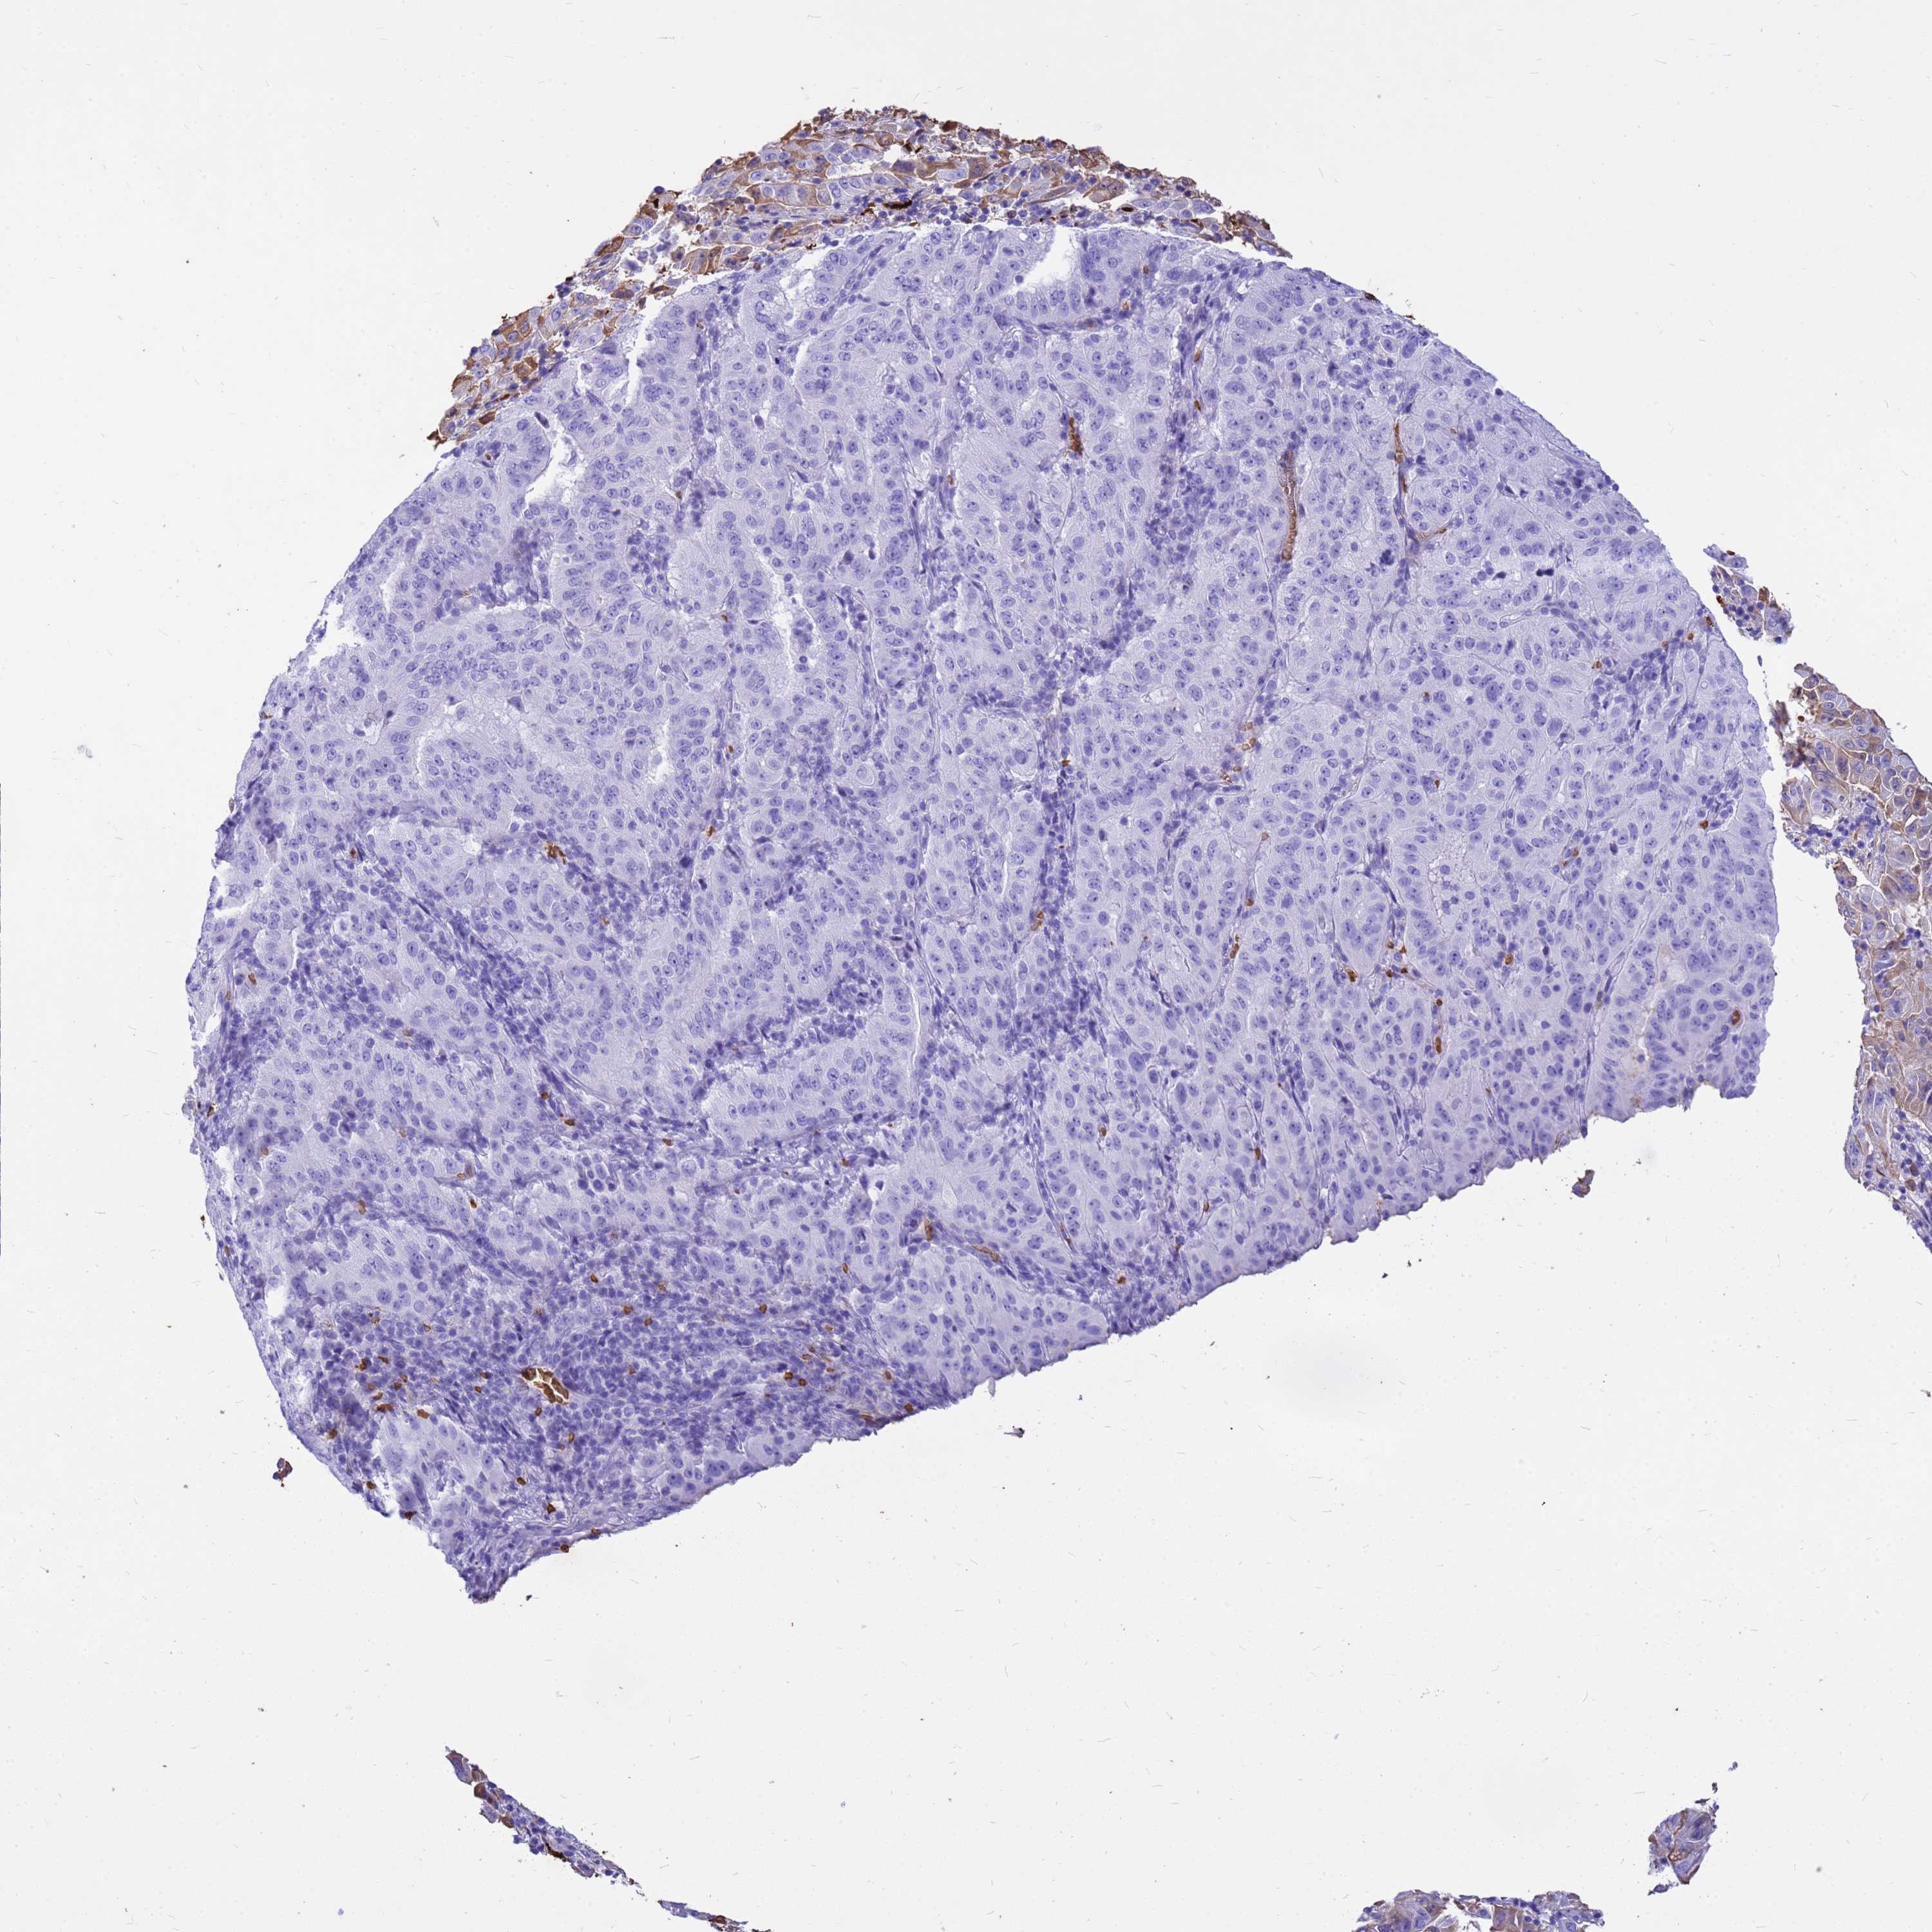

PANCREATIC CANCER - Protein expressioni

A mouse-over function shows sample information and annotation data. Click on an image to view it in a full screen mode. Samples can be filtered based on level of antibody staining by selecting one or several of the following categories: high, medium, low and not detected. The assay and annotation is described here.

Note that samples used for immunohistochemistry by the Human Protein Atlas do not correspond to samples in the TCGA dataset.

Antibody stainingi

Antibody staining in the annotated cell types in the current human tissue is reported as not detected, low, medium, or high, based on conventional immunohistochemistry profiling in selected tissues. This score is based on the combination of the staining intensity and fraction of stained cells.

Each image is clickable and will lead to virtual microscopy that enables deeper exploration of all samples and also displays staining intensity scores, fraction scores and subcellular localization as well as patient and tissue information for each sample.

Antibody HPA043780

Antibody CAB032534

Adenocarcinoma, NOS